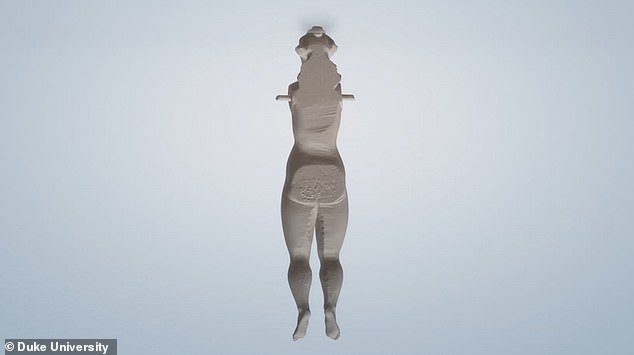

وقام الباحثون الأمريكيون، بمسح الأجزاء الداخلية لـ 22 من التماثيل وكشفوا عن تفاصيلها من الداخل، لافتين إلى أنهم سوف يقومون بإنشاء نماذج ثلاثية الأبعاد للعارضين من أجل التفاعل بشكل أفضل مع القطع الفريدة من التاريخ الطبي دوت التعرض لخطر التلف.

ومن خلال إجراء عمليات المسح الضوئى ثلاثى الأبعاد للعارضين، تمكن الدكتور شوارتز وزملاؤه من معرفة المزيد حول كيفية صنع التحف الطبية – ويأملون فى نسخ تماثيل متماثلة ثلاثية الأبعاد يمكن للجمهور التفاعل معها بالفعل، غالبًا ما تستخدم الأشعة السينية والأشعة المقطعية - كتلك المستخدمة في المستشفيات - لفحص القطع الفنية الهشة أوالقديمة، والتي يمكن استخدامها دون الإضرار بالموضوع.

تماثيل الاقزام